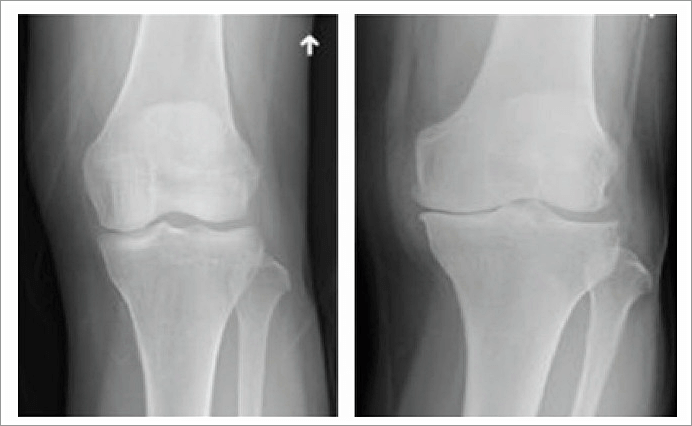

관절은 뼈와 뼈 사이가 부드럽게 운동할 수 있도록 연골, 관절낭, 활막, 인대, 힘줄, 근육 등으로 구성되어 있으며, 움직임에 따라 발생하는 충격을 흡수하는 역할을 한다. 관절염은 여러 가지 원인에 의해 관절에 염증이 생긴 것으로 이로 인해 나타나는 대표적인 증상은 관절의 통증이다.

관절은 쓰면 쓸수록 닳는 신체 부위다. 특히 무릎은 우리 몸에서 하중 지탱으로 압력을 가장 많이 받는 부위라 관절염이 생기기 쉽다. 무릎 연골은 탄력이 있어 뼈와 뼈 사이에서 쿠션 역할을 해 마찰이 생기는 걸 방지해준다. 근육의 수축 및 이완 작용을 보조하는 역할을 하기도 한다.

정상적인 연골은 뼈 표면에 3~5mm정도로 푹신하고 미끌미끌한 형태를 유지하는데, 이 연골이 충격이나 과사용 등으로 벗겨지면, 관절이 스스로 보호하려는 염증 물질을 배출하면서 시리고 아픈 느낌이 생긴다 연골 중 무릎의 체중을 받쳐주는 반월상 연골이 손상되면 퇴행성관절염이 특히 잘 생긴다.

반월상 연골은 무릎에 전달되는 체중의 40~60%를 흡수해주고 관절 안정성을 유지하는데, 나이가 들수록 약해지며 쉽게 찢어진다.반월상 연골이 손상되면 무릎이 뻣뻣하거나 힘이 빠지는 느낌이 들지만 손상 부위가 작으면 초기에는 심각하지 않아 방치하기 쉽다.